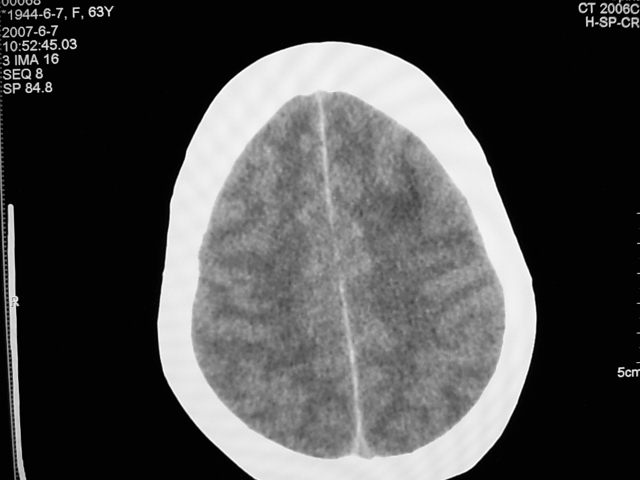

患者 女 63岁,近几周感觉头部不适来查体。

请调骨窗。多考虑前中颅窝脑外肿瘤,脑膜瘤、淋巴瘤或血管外皮瘤均有可能,蝶嵴脑膜瘤可能性最大。

左侧额颞部巨大肿块,平扫呈略高密度,增强明显强化,周围水肿明显,左侧侧脑室受压,右侧侧脑室扩大,中线明显右移,局部骨质增厚,支持脑膜瘤、大脑廉下疝。